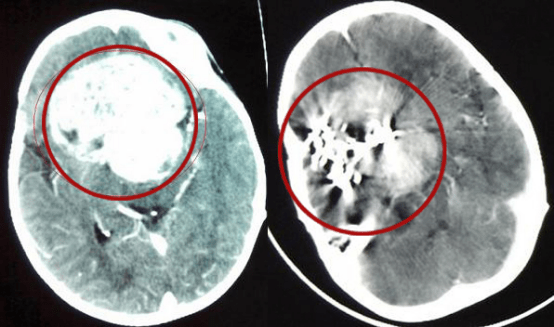

>▂< 一台7.5个亿,开机1分钟烧4万块钱!这种医疗器械凭什么那么贵?一次完整的质子治疗可能需要花费20万美元(约合140万元人民币)。而在中国,质子治疗的费用则会根据医院的不同有所差异,部分医院的费用甚至超过每次治疗17万元人民币。这样的费用对于大部分普通家庭来说,无疑是一笔巨大的支出。高昂费用的原因,正如前文所提到的,质子刀的设备...